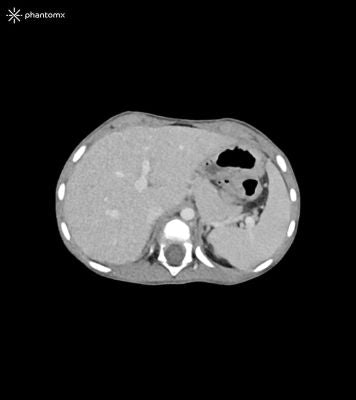

Description

This phantom simulates the contrast-enhanced thorax, abdomen and pelvis of a 3-year-old child in the portal venous phase. It covers the sixth cervical vertebra to the perineum.

The phantom can be used in CT (including CBCT) and X-ray imaging to evaluate and optimize imaging performance and post-processing applications, including AI-enabled applications. It is also suited for training purposes.

The phantom provides a detailed and realistic simulation of soft and bone tissue. Air voids including those of the lungs are filled with a cellulose-polymer composite of approx. -160 HU.